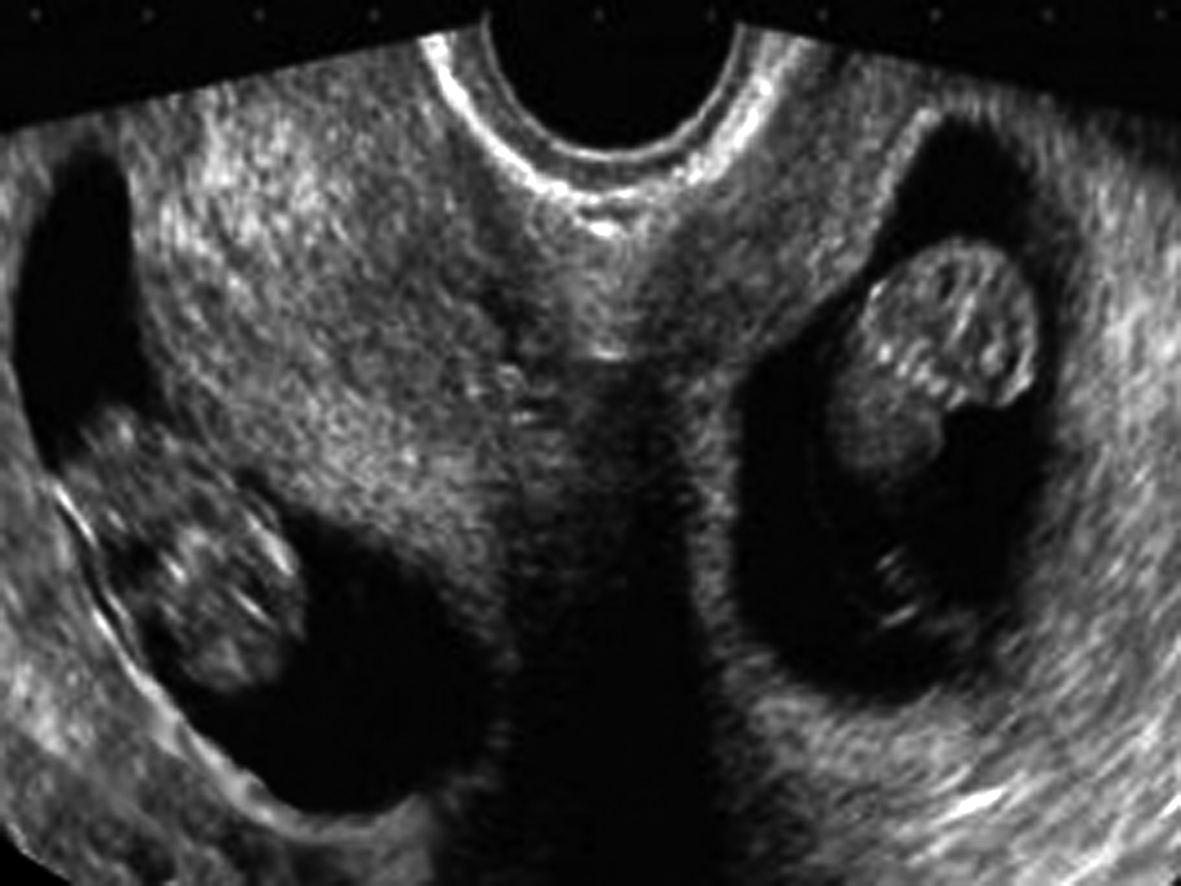

3.卵黄囊 卵黄囊数可以确认胚胎数目。超声检查可以早地显示卵黄囊(图2)。但有时早期显示卵黄囊和羊膜可能有一定的难度,或卵黄囊显示时间较短而错过显示的时机。单绒毛膜囊单羊膜囊双胎妊娠多数仅有一个卵黄囊,极少数可能显示部分分开的卵黄囊。因此,早期在孕囊内显示2个卵黄囊可以提示为双胎妊娠,但1个卵黄囊并不是单胎妊娠的绝对声像图特征,应当在以后的检查中继续观察,评估胚胎的个数,以明确是否为单羊膜囊双胎妊娠。

图2多胎妊娠声像图 A:TVU显示两个孕囊及各自的卵黄囊回声 B:TVU显示3个孕囊及各自的胚胎结构